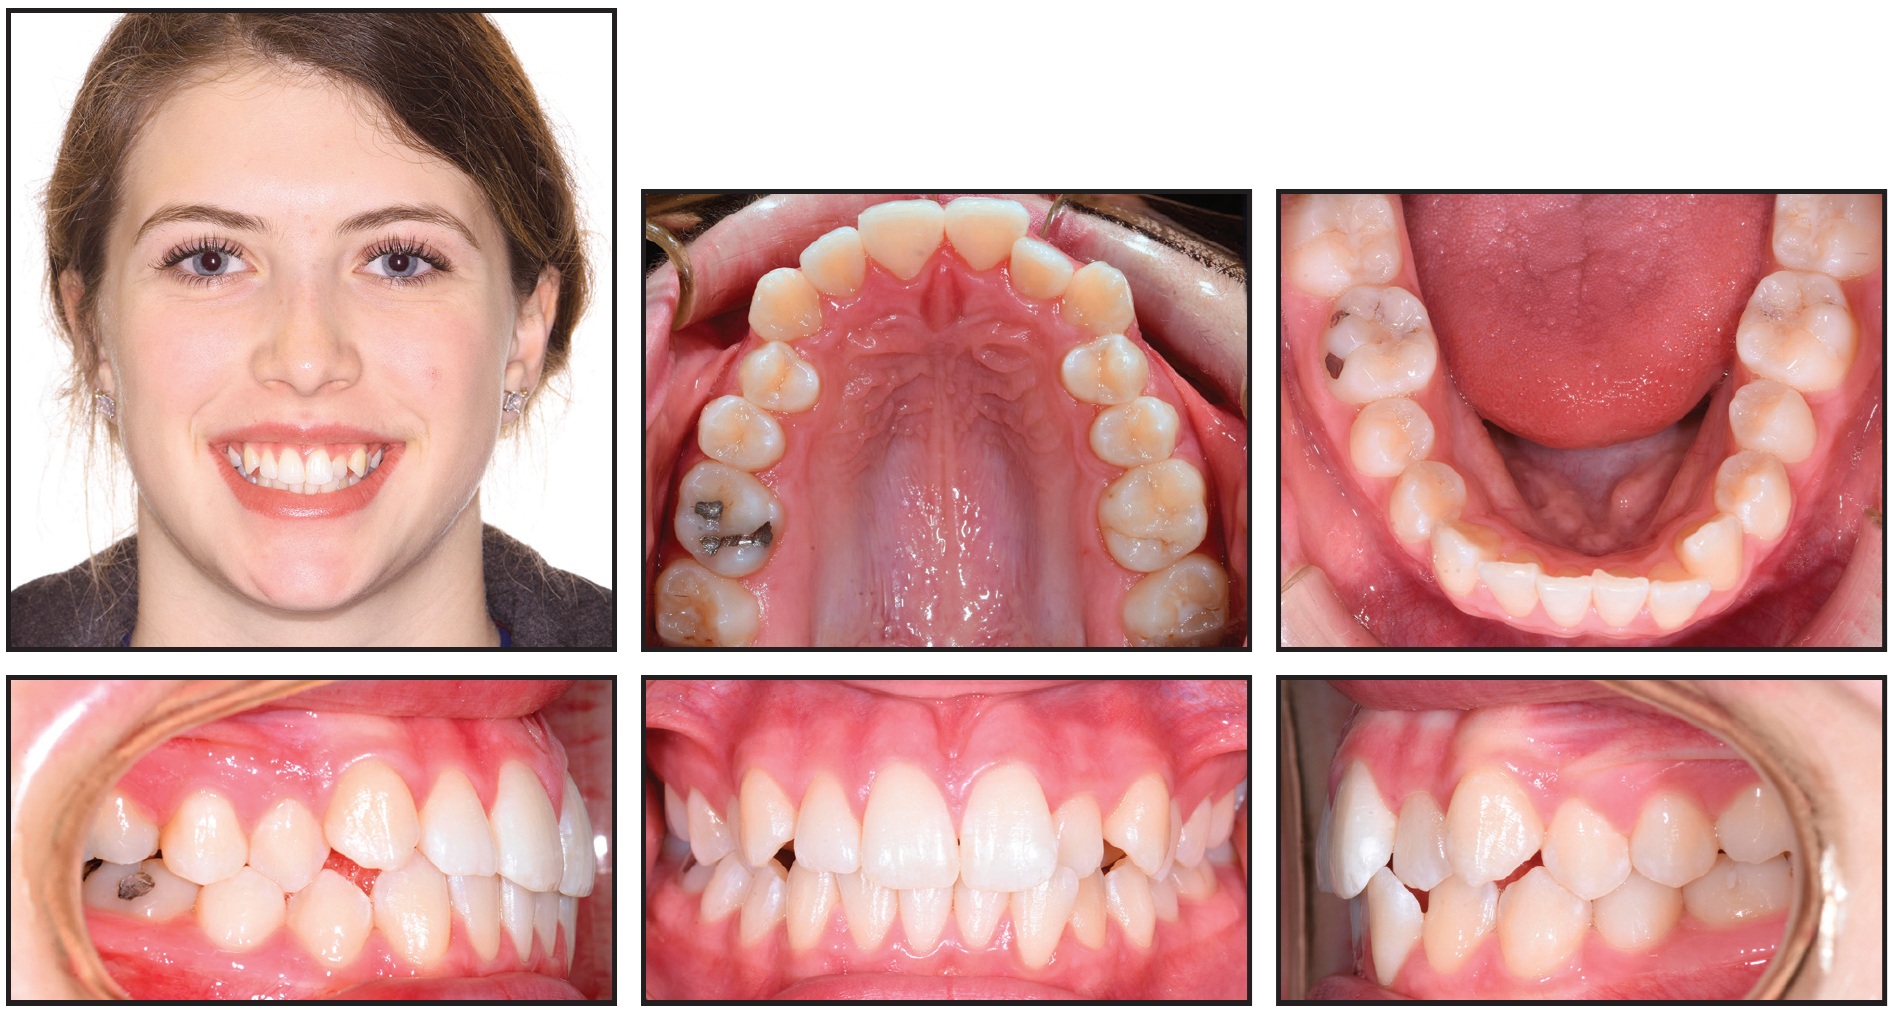

A 22-year-old female presented for treatment of minor crowding, a moderately deep bite, and narrow dental arches (Fig. 4).

Fig. 4 Case 1. 22-year-old female patient with lower midline shift, mild crowding in both arches, asymmetrical upper archform, Class I relationship on left side, and one-fourth- to one-half-unit Class II relationship on right before treatment.

Examination found a lower midline shifted 2mm to the right; mild crowding in both arches; an asymmetrical, skewed upper archform; and lips that were slightly retrusive relative to the E-line (Table 1).

A good facial profile and balance were noted, along with normal upper incisor positions and lingual tipping in the buccal segments. The molar and canine relationships were diagnosed as Class I on the left and one-fourth- to one-half-unit Class II on the right.